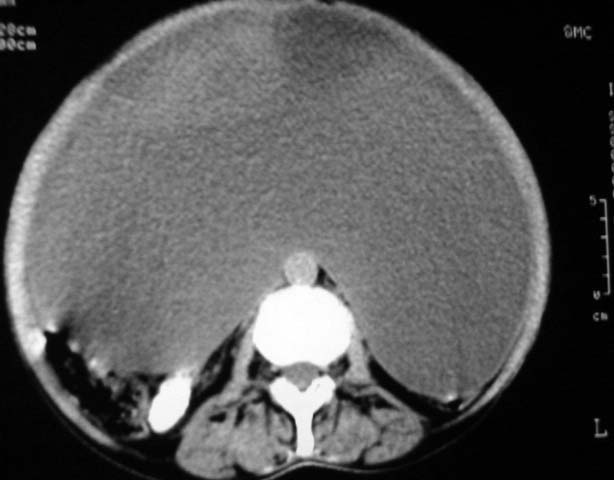

女,75岁,腹部胀大半年余,无其他症状。

考虑来源与卵巢的巨大囊腺瘤或囊肿。

ct值各是多少?考虑卵巢囊肿或囊腺瘤。

考虑来源卵巢巨大黏液性囊腺瘤。